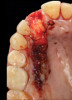

8. Tooth No. 8 with diagnosis of Grade III socket, requiring extraction followed by guided bone regeneration and a rotated pedicle flap to gain hard and soft tissue for future implant placement.

Figure 8

9. Tooth No. 8 with diagnosis of Grade III socket, requiring extraction followed by guided bone regeneration and a rotated pedicle flap to gain hard and soft tissue for future implant placement.

Figure 9

10. Tooth No. 8 with diagnosis of Grade III socket, requiring extraction followed by guided bone regeneration and a rotated pedicle flap to gain hard and soft tissue for future implant placement.

Figure 10

11. Tooth No. 8 with diagnosis of Grade III socket, requiring extraction followed by guided bone regeneration and a rotated pedicle flap to gain hard and soft tissue for future implant placement.

Figure 11